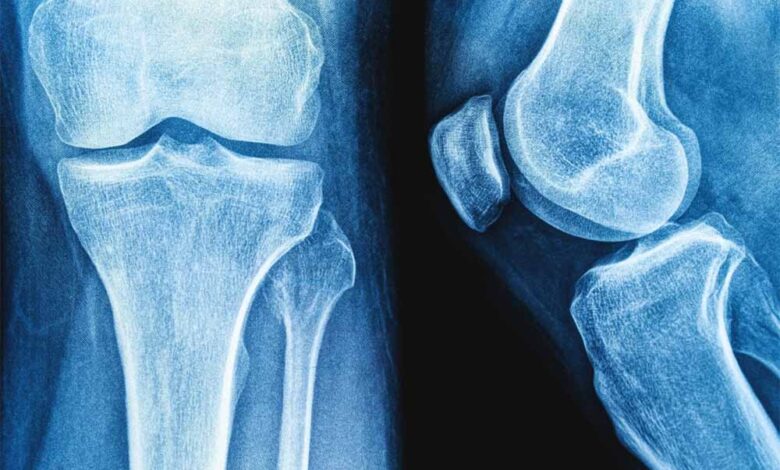

राष्ट्रीय प्रौद्योगिकी संस्थान (एनआईटी) राउरकेला के शोधकर्ताओं ने मानव शरीर में पाई जाने वाली प्राकृतिक शर्करा जैसे अणु हड्डियों के निर्माण और मरम्मत के लिए जिम्मेदार प्रोटीन, बोन मॉर्फोजेनेटिक प्रोटीन-2 के व्यवहार को कैसे प्रभावित कर सकती है? इसका पता लगाया है।

प्रतिष्ठित पत्रिका बायोकैमिस्ट्री में प्रकाशित इस शोध के निष्कर्षों का उपयोग हड्डी और उपास्थि पुनर्जनन के उन्नत उपचार, बेहतर इम्प्लांट और अधिक प्रभावी प्रोटीन-आधारित दवाओं के विकास में किया जा सकता है। प्रोटीन मनुष्य के शरीर में विभिन्न कार्य करते हैं। टिश्यू के निर्माण और रासायनिक प्रतिक्रियाओं में सहयोग देने से लेकर कोशिकाओं के बीच संकेतों के रूप में कार्य करने तक बड़ी जिम्मेदारी निभाते हैं।

हालांकि सर्वोत्तम उत्पादकता के लिए इनका त्रि-आयामी आकृतियों में सटीक मुड़ना या खुलना आवश्यक है। प्रोटीन क्यों और कैसे खुलते हैं? यह समझना जीव विज्ञान का एक प्रमुख लक्ष्य है। इसका प्रभाव चिकित्सा, जैव प्रौद्योगिकी और ड्रग डिलिवरी पर पड़ता है। इस संदर्भ में हड्डी और उपास्थि के निर्माण, चोटों को ठीक करने और स्टेम कोशिकाओं को अस्थि-निर्माण कोशिकाओं में परिणत करने में बीएमपी-2 महत्वपूर्ण भूमिका निभाता है।

प्रो. हरेकृष्ण साहू ने इस शोध के निष्कर्षों और इससे संभावित वास्तविक लाभों के बारे में बताया कि बीएमपी-2 मनुष्यों में पाया जाने वाला एक महत्वपूर्ण प्रोटीन है। यह बोन टिश्यू के ग्लाइकोसामिनोग्लाइकन से सम्पन्न बाह्यकोशिकीय मैट्रिक्स में मौजूद रह कर हड्डियों के निर्माण और पुनर्निर्माण में बुनियादी भूमिका निभाता है।